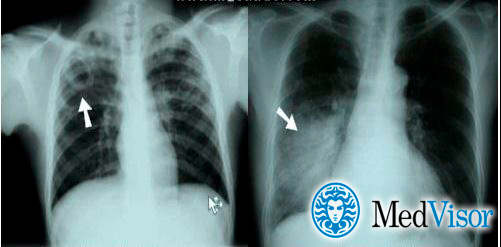

Рентген

Опасным воспалением при туберкулезе или пневмонии считается верхнедолевой очаг поражения, который чаще всего поражается микобактериями.

При пневмонии обнаруживаются на рентгене изменения, позволяющие отличить ее от туберкулеза:

1. Уплотнение (инфильтрация) участка легких с неявными, размытыми очертаниями или в виде дымки (характерно для снимков при острой форме).

2. Усиление легочного рисунка (при интерстициальной форме).

При верхнедолевой левосторонней пневмонии поражается до 5 долей легкого. Заболевания этого органа протекают тяжелее, чем правосторонняя пневмония, при которой поражается 1-3 участка.

Флюорографией при пневмонии чаще выявляется поражение нижних и средних частей с изменениями корня легкого.

При туберкулезном инфицировании изменения отмечаются в верхней части легкого, отличаются четкими очертаниями, без видимых изменений корня.

На рентгенограмме обнаруживается при туберкулезе:

1. Диссеминированном. Множество мелких, хорошо очерченных, или более крупных пятен, есть каверны.

2. Очаговом. Уплотнение находится не ниже 2 ребра, вокруг могут быть фиброзные тяжи, усилен легочный рисунок.

3. Инфильтративном. Уплотнения правильной округлой формы на рентгеновском снимке в верхней легочной доле.

4. Казеозной пневмонии. Множество полостей распада с неровными краями, очагами отсева, смещением средостения в больную сторону груди.

Отличия пневмонии от туберкулеза на рентгене

При пневмонии на рентгенограмме обычно видны инфильтраты и уплотнения. Типичное изображение представляет собой однородное или неоднородное белое пятно в основании пораженного легкого, либо в средней его трети. Типичным также считается плевральный выпот – скопление жидкости в плевральной полости – на той же стороне, что и очаг пневмонии.

Туберкулез обычно проявляется в виде кавитации (пустоты) в верхней части легкого. На снимке она выглядит как округлая полость. При этом также имеет место плевральный выпот.

Впрочем, отличия пневмонии от туберкулеза могут быть не такими очевидными как на снимке. Иными словами, одна флюорография не является показательной.